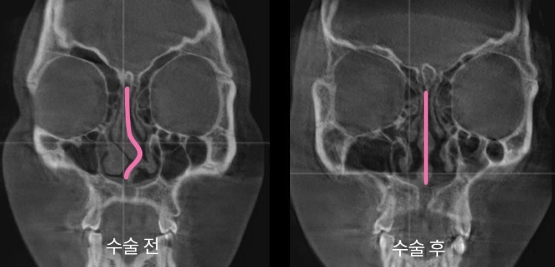

아이디병원은 대학병원에서 사용하는 첨단 3D-CT를 통한 정확한 검사와 이비인후과 및 성형외과, 마취통증의학과 등 전문의 협진을 통해 당일 한 번에 모든 과정을 수술하는 시스템을 구축했다. 동시에, 코 외관(골절된 코뼈 교정)과 코 내관(휘어진 비중격 교정)을 각 전문의가 협진으로 수술하는 형태를 구축했다.